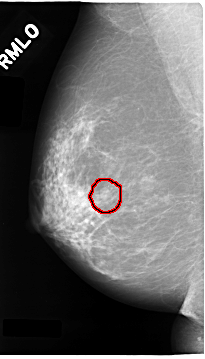

C_0024_1.RIGHT_MLO

FILE: C_0024_1.RIGHT_MLO.OVERLAY

TOTAL_ABNORMALITIES 1

ABNORMALITY 1

LESION_TYPE MASS SHAPE OVAL MARGINS CIRCUMSCRIBED

ASSESSMENT 3

SUBTLETY 5

PATHOLOGY BENIGN

TOTAL_OUTLINES 1

BOUNDARY